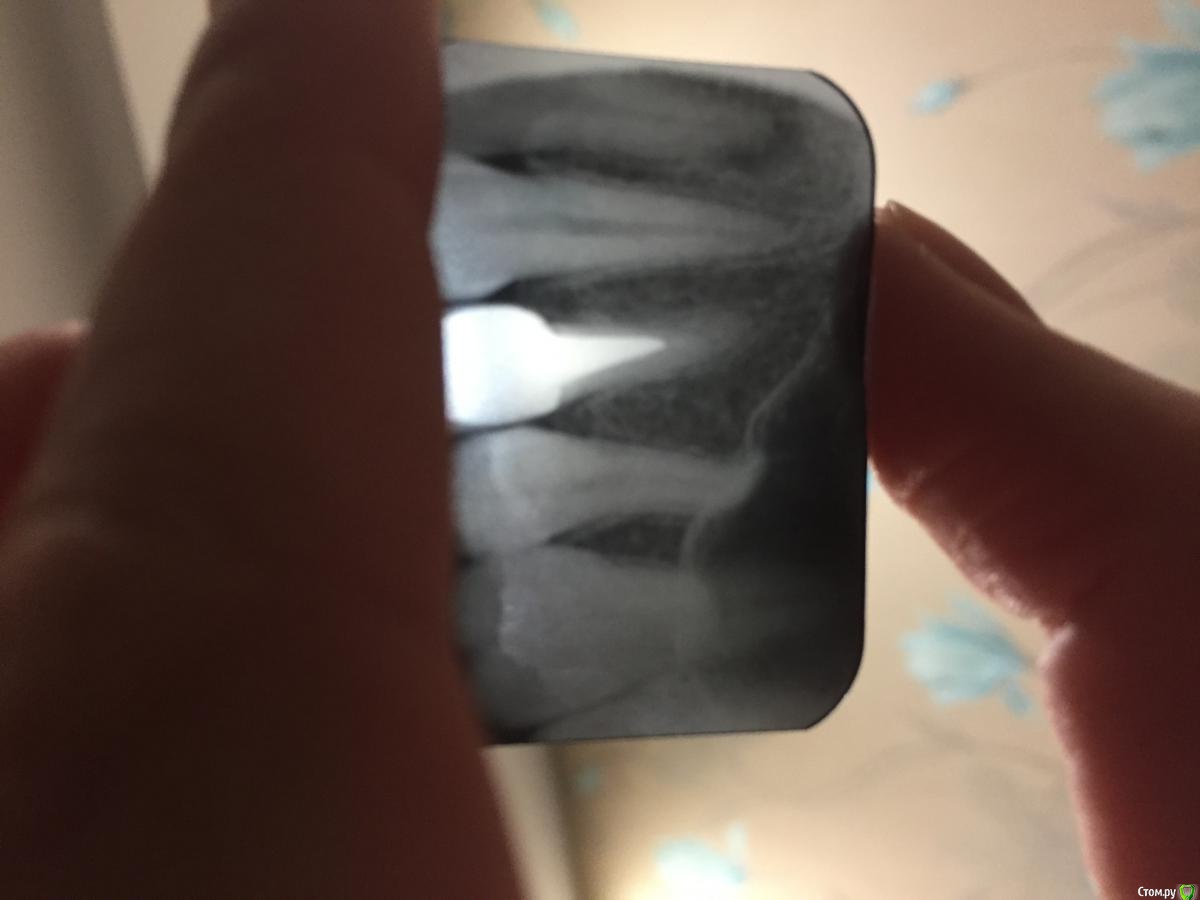

Bobotik Опубликовано 7 февраля, 2017 Поделиться Опубликовано 7 февраля, 2017 Здравствуйте, уважаемые доктора. Возникла проблема с 24 зубом. С 2008 года стоит вкладка с коронкой, один раз коронка выпала вместе с вкладкой в 2012 году, Ее просто приклеили на место, второй раз выпала в сентябре прошлого года-сделали тоже самое. Сейчас появилась припухлость дёсны вокруг зуба и неприятный запах из под коронки, также небольшой дискомфорт при нажатии! Что посоветуете? Удалять и имплант? Снимок прилагаю! Ссылка на комментарий

krokomot Опубликовано 7 февраля, 2017 Поделиться Опубликовано 7 февраля, 2017 Учитывая снимок и частоту выпадений скорее всего имеется трещина коня и ничего уже его не спасет, если это так, в таком случае корень удаляется и на его место устанавливается имплантат. для точного определения наличия трещины нужен очный осмотр 2 Ссылка на комментарий

Bobotik Опубликовано 8 февраля, 2017 Автор Поделиться Опубликовано 8 февраля, 2017 Учитывая снимок и частоту выпадений скорее всего имеется трещина коня и ничего уже его не спасет, если это так, в таком случае корень удаляется и на его место устанавливается имплантат. для точного определения наличия трещины нужен очный осмотр Спасибо за ответ! Правильно ли я вижу по снимку, что канал после вкладки вообще не запломбирован? Так и должно быть или я чего то не понимаю? Ссылка на комментарий

krokomot Опубликовано 8 февраля, 2017 Поделиться Опубликовано 8 февраля, 2017 По вашему снимку сложно судить о качестве пломбировки какала он должен быть в другой прекции 1 Ссылка на комментарий